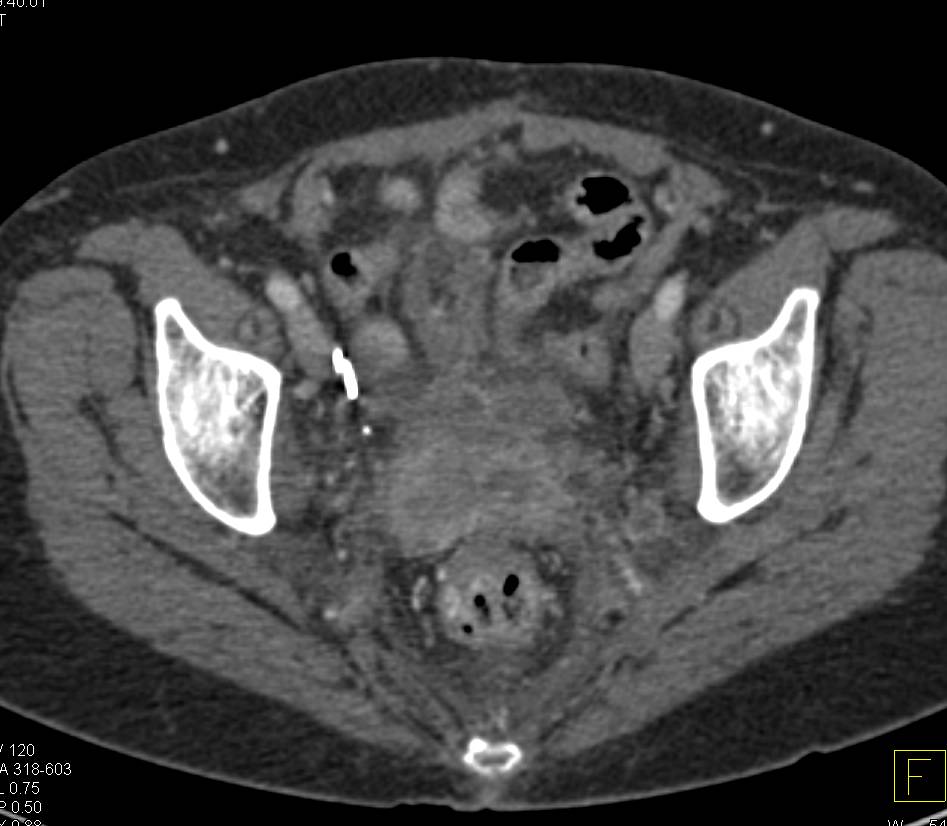

Pelvic Abscess